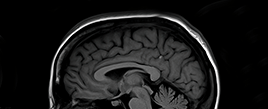

Brain & Spine Care

Our highly-trained neurosurgeons and neurologists treat all conditions of the brain and spine. With six hospitals in the Portland, OR and Vancouver, WA areas, we provide the highest-level care and convenience.